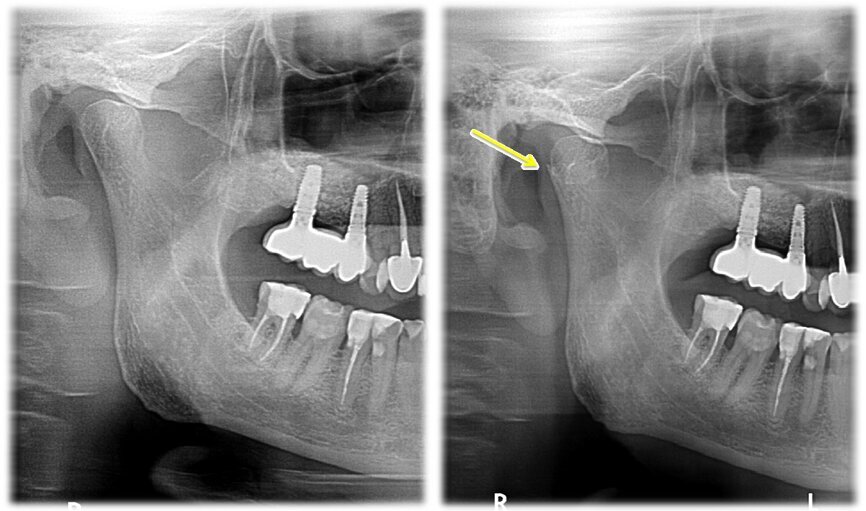

Zdjęcie panoramiczne w tym przypadku nie stanowiło jednoznacznej metody diagnostycznej. Dopiero, porównując zdjęcie po urazie ze zdjęciem wykonanym przed urazem, widoczne było skrócenie gałęzi żuchwy po stronie prawej. Dzięki wykorzystaniu przekrojów osiowych i transsektalnych w badaniu tomografem stożkowym o zmiennym polu obrazowania ustalono przyczynę zaburzeń okluzji u pacjenta oraz w sposób jednoznaczny określono uszkodzenie w obrębie stawu skroniowo-żuchwowego. Po analizie zdjęcia tomograficznego zdiagnozowano u pacjenta złamanie wyrostka kłykciowego żuchwy po stronie prawej. Co istotne, diagnostyka przeprowadzona na podstawie zdjęcia pantomograficznego nie dawało tak ewidentnego wyniku, jak obrazowanie stawu skroniowo-żuchwowego z wykorzystaniem obrazowania 3D. Bez porównania zdjęcia panoramicznego przed i po urazie dostrzeżenie nieprawidłowości było trudne dla niedoświadczonego lekarza.

Ryc. 4_ Zdjęcie pantomograficzne przed urazem (po lewo) i po urazie (po prawo).